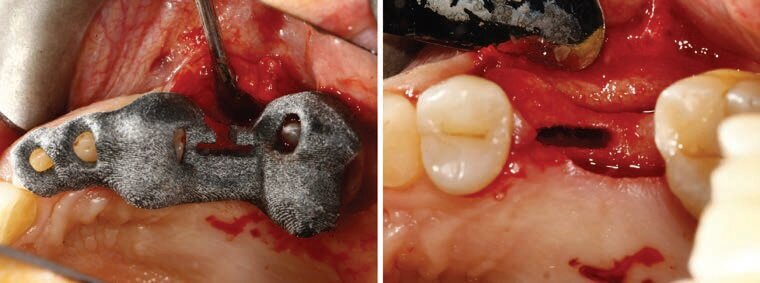

A causa dell’inclinazione dell’osso rispetto ai denti adiacenti (processo caratteristico che si verifica a seguito del riassorbimento della corticale vestibolare), si nota che il posizionamento dell’impianto necessita di un’inclinazione protesica in senso mesio-distale per la presenza della parete mesiale del seno mascellare e vestibolo-palatale per il riassorbimento orizzontale. Tali inclinazioni risultano essere differenti dall’inclinazione che l’anatomia ossea “suggerisce” al chirurgo e quindi è opportuno ricorrere alla metodica guidata per poter riprodurre la posizione della progettazione implantoprotesica predeterminata. Per realizzare una dima chirurgica REX Guide, è possibile disegnarla con il software Guide Design – Medialab** che al suo interno dispone della chiave per guidare gli inserti PIEZOSURGERY necessari per ottenere la preparazione del sito implantare. Dopo aver disegnato la dima chirurgica sarà possibile esportare il file STL per poterlo stampare direttamente con una stampante 3D. Per la preparazione del sito implantare sarà quindi utilizzata la dima chirurgica REX Guide (Fig. 5) con gli inserti PIEZOSURGERY utilizzati in sequenza secondo il protocollo REX, alternandoli alle relative fit-gauges per il controllo della profondità e della preparazione.

Fig. 5 - Inserimento in situ della dima chirurgica e sito preparato per accogliere l’impianto REX progettato.